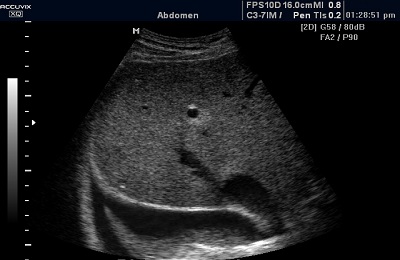

Во время процедуры обследования ультразвуковые волны проходят сквозь ткани легких и благодаря различию в их структурах, волны отражаются и улавливаются датчиком аппарата УЗИ. После того как данные обработаны, они передаются на экран аппарата, где специалист наблюдает их в виде черно-белой картинки.

Процедура проводится, когда пациент сидит на стуле, в комфортной для него позе, с оголенным по грудь туловищем. На его грудь наносят специальный гель для плотного контакта тела с датчиком. Датчик (с приблизительной частотой 1,8-7,5 МГц) строго под прямым углом устанавливают в межреберье.

После этого специалист составляет характеристику эхогенности. Длительность подобной процедуры составляет от десяти до двадцати минут. В этом случае все зависит от того, обнаружит ли врач патологии. А если таковых обнаружено не будет, пациент сразу узнает о благоприятном результате. Закончив обследование, специалист напишет для него заключение и приложит полученные снимки.

Плевральный выпот представляет собой накопление в полости плевры жидкости. Выпот – это водянистое образование, и поэтому при УЗИ он незаметен, но зато плевра хорошо показывает границы скопления жидкости, которые замечаются при дыхании пациента.

Определение жидкости, накопившейся в полости плевры, важно для результата диагностики. При исследовании метод сонографии не всегда эффективен, т.к. в транссудате нет веществ, способствующих его выявлению.

Ввиду этого подобный транссудат называют анэхогенным. По количеству этой жидкости судят о тяжести гипотериоза или цирротических очагах в печени. Скопление белков в экссудате дает шанс его заметить при обследовании ультразвуком.